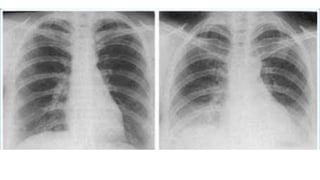

Underexposure

In an under exposed

chest radiograph, the

cardiac shadow is

opaque, with little or no

visibility of the thoracic

vertebrae.

The lungs may appear

much denser and whiter,

gives appearance of

infiltrates.

Overexposed

With greater exposure of the

chest radiograph, the heart

becomes more radiolucent

and the lungs become

proportionately darker.

Often gives the appearance

of lacking lung tissue, as

would be seen in a condition

such as emphysema.